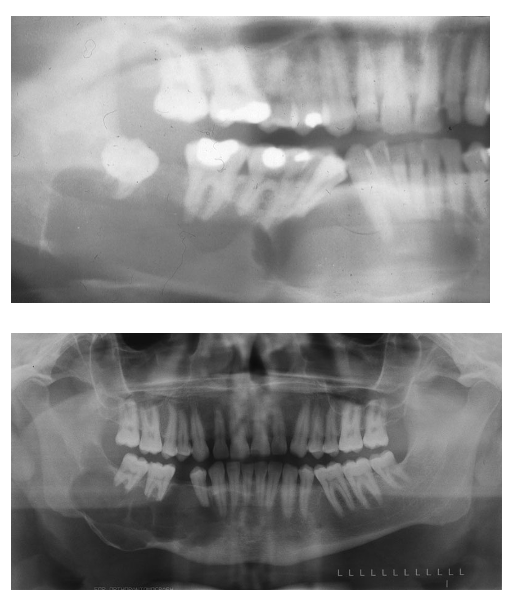

what is this

1) explain clinical

2) explain radiographic presentation

3) explain histopathology

4) explain cyst content

5) treatment